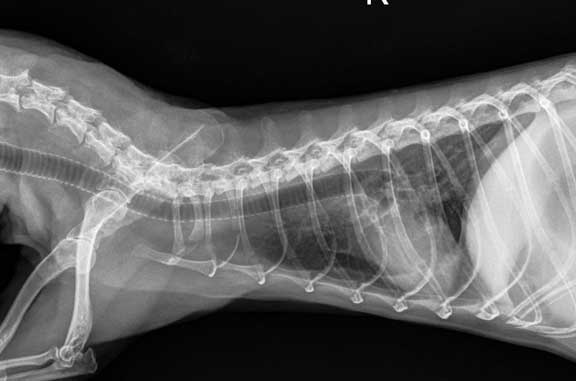

A pre-operative radiograph (X-ray) might also be taken if your doctor thinks it is indicated after the physical exam. The white structure in this chest radiograph is the heart, and the horizontal dark tube from left to right is the trachea (windpipe). This is where we put the breathing tube (endotracheal tube) when we administer oxygen and anesthesia.